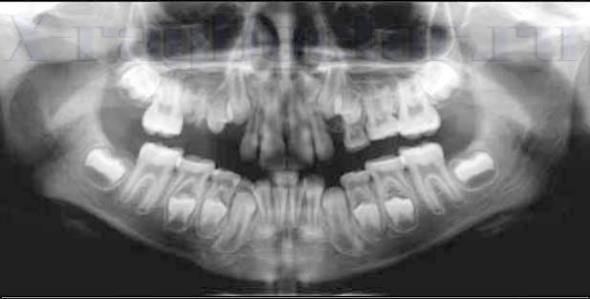

Рентген зубов у детей

В детской стоматологии без рентгенологической диагностики обойтись фактически невозможно. Современные аппараты обеспечивают минимально возможную лучевую нагрузку, поэтому процедура абсолютно безвредна для ребенка.

Ортопантомограмму желательно первый раз провести в возрасте 5-6 лет, когда начинается процесс замены зубов молочного прикуса на постоянные.

Исследование помогает выявить:

- врожденные пороки развития;

- патологии окклюзии (прикуса);

- чрезмерное или недостаточное развитие одной из челюстных костей;

- патологии костных структур;

- сверхкомплектные зубы;

- адентию.

На снимке можно хорошо рассмотреть состояние зачатков постоянных зубов. Выявление ортодонтических патологий позволяет подобрать аппарат, оптимально подходящий для коррекции той или иной аномалии прикуса. Ранняя диагностика способна существенно сократить сроки лечения. Известно, что профилактическое посещение стоматолога необходимо 1 раз в полгода. При отсутствии показаний проводить рентгенографию можно и реже.